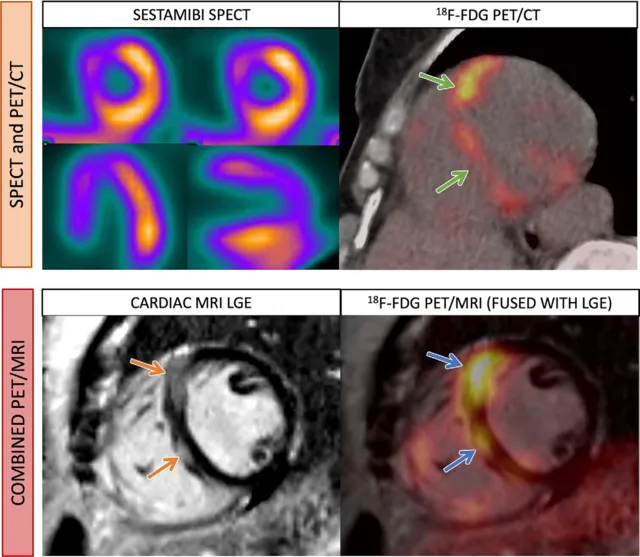

MPI & Cardiac MRI - Hot Spots & Heart Scars

- Myocardial Perfusion Imaging (MPI - SPECT/PET): Assesses myocardial perfusion & viability.

- Tracer uptake = viable, perfused tissue. Defects = ↓flow/viability.

- Tracers: $^{99m}$Tc-Sestamibi/Tetrofosmin (SPECT); $^{82}$Rb, $^{13}$N-Ammonia (PET perfusion); $^{18}$F-FDG (PET viability).

- Key Patterns:

- Ischemia: Reversible defect (stress defect, rest normal).

- Infarct: Fixed defect (stress & rest).

- Hibernating: ↓Perfusion, preserved/↑FDG (mismatch).

- Cardiac MRI (CMR): Gold standard for function, mass, viability.

- LGE (Late Gadolinium Enhancement): Identifies "heart scars" (infarcts).

- Ischemic LGE: Subendocardial → transmural.

- Viability (transmurality): <25% (good), >50% (poor recovery).

- MVO (Microvascular Obstruction): Dark core in LGE; poor prognosis.

- T2W: Myocardial edema (acute MI).

⭐ LGE in CMR: Subendocardial enhancement is the hallmark of ischemic injury; its transmural extent (e.g., >50% thickness) predicts poor functional recovery post-revascularization.